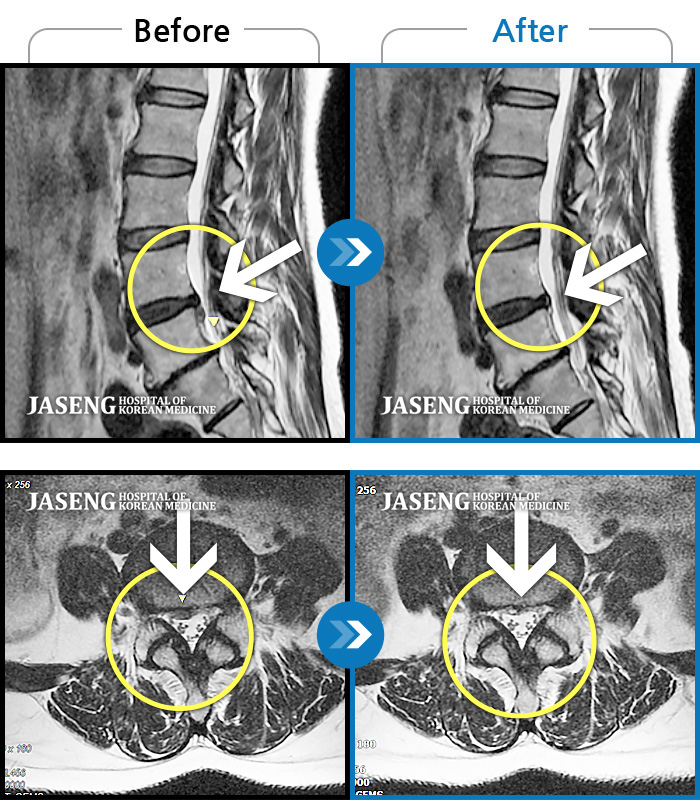

MRI 치료사례

허리디스크로 연골이 거의 없다고 진단 받음